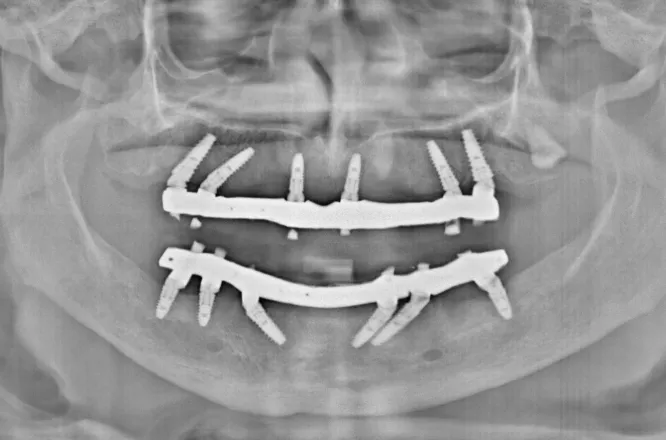

At iCube Dental, we use advanced CBCT and CAD/CAM technology to ensure precision, comfort and long-lasting results. Our implants are designed to restore your smile’s strength, stability and appearance – helping you eat, speak and smile with complete confidence.

Replacing missing teeth with dental implants at iCube Dental is a precise and technique-sensitive procedure that requires professional expertise and careful planning.

A high-quality titanium implant is securely placed into the jawbone at the site of the missing tooth, creating a strong and stable foundation for a crown or artificial tooth. This design closely mimics the structure and function of a natural tooth, allowing you to chew, bite, and speak comfortably. Dental implants at iCube Dental not only restore your smile but also help maintain jawbone health, prevent bone loss, and improve overall facial structure.